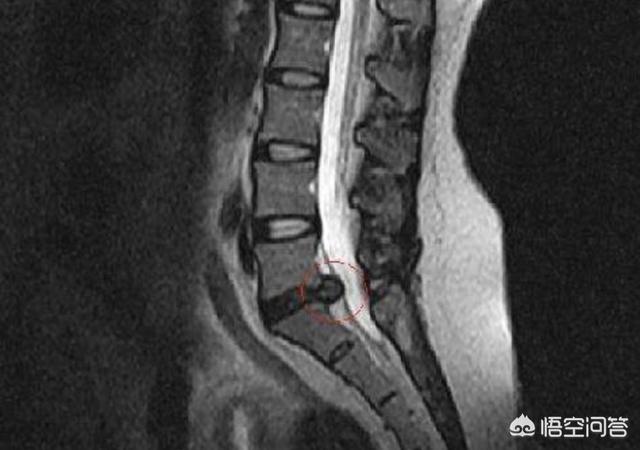

腰椎间盘突出症,椎间盘突出的患者,有的由于突出大小和位置、方向问题,有的会在弯腰的姿态下,对后方的硬膜囊压力增强,诱发疼痛,多数平时咳嗽打喷嚏也会疼,你的状况这个概率不高!